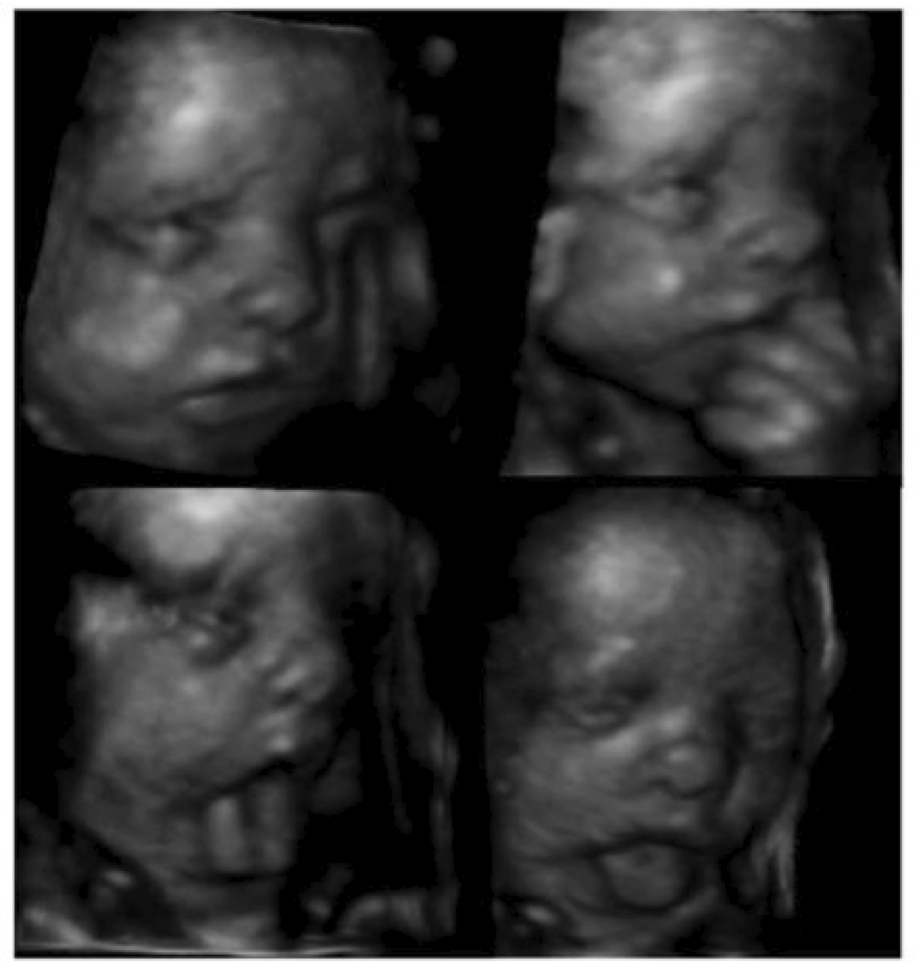

Here, we look at the single instance of neonatal facial imitation for which there exists robust evidence of imitation—namely, tongue protrusion. At least prima facie, Infant tongue protrusion appears to have the hallmark features of a neurodevelopmental behavior: it occurs spontaneously in utero along with a number of other facial expressions—mouth opening, grimacing, finger sucking, and yawning; it is a rhythmic, spontaneous motor activity that begins and ends at predictable periods on perinatal development; its failure to extinguish during the neonatal period correlates with neurological/developmental disability; and it can reappear later in life as a result of neural trauma or age-related neural deterioration. It is also seen in other Old World Primates and has roughly the same characteristics in these other species.

In utero expressions of the fetus: grimacing, finger sucking,tongue protrusion to the side, and tongue protrusion in the midline, also called tongue thrust(Kuriak et al. 2004.)